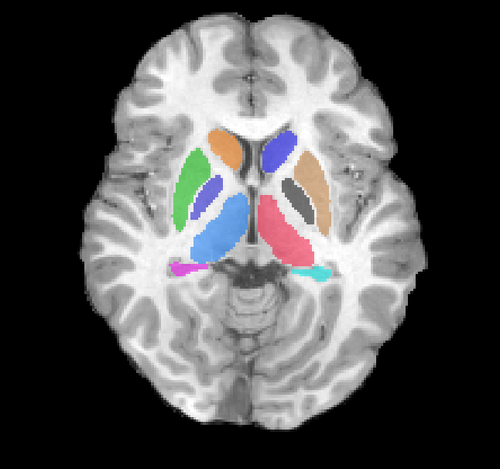

Slicer Shape AnaLysis Toolbox (SlicerSALT) is a standalone version of Slicer specifically for shape analysis, currently under development. One aspect of the project is the validation of the tools to be included in SlicerSALT. In this project, we will begin validating the shape regression component with a longitudinal database of subcortical structures. |

Illustrations